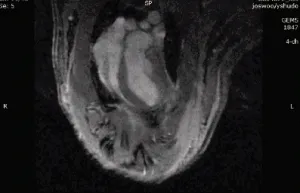

随后,研究人员开始在活体动物身上进行对照实验:他们为小鼠进行了开胸手术,人为阻断心脏血液供给来模拟心脏病发时的状况。此时,再将藻类注入小鼠心脏并进行光照,效果是显著的,藻类产生的氧气马上被缺氧的心肌细胞吸收。